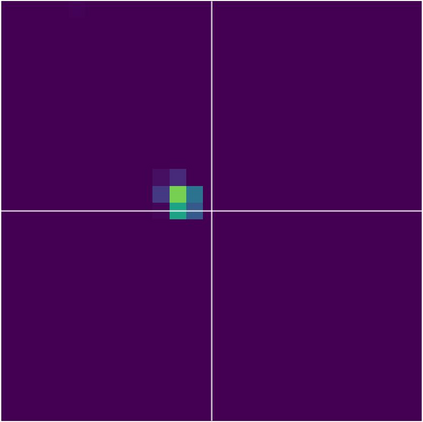

Various imaging modalities allow for time-dependent image reconstructions from measurements where its acquisition also has a time-dependent nature. Magnetic particle imaging (MPI) falls into this class of imaging modalities and it thus also provides a dynamic inverse problem. Without proper consideration of the dynamic behavior, motion artifacts in the reconstruction become an issue. More sophisticated methods need to be developed and applied to the reconstruction of the time-dependent sequences of images. In this context, we investigate the incorporation of motion priors in terms of certain flow-parameter-dependent PDEs in the reconstruction process of time-dependent 3D images in magnetic particle imaging. The present work comprises the method development for a general 3D+time setting for time-dependent linear forward operators, analytical investigation of necessary properties in the MPI forward operator, modeling aspects in dynamic MPI, and extensive numerical experiments on 3D+time imaging including simulated data as well as measurements from a rotation phantom and in-vivo data from a mouse.